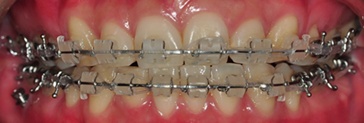

그 결과~ 상악 하악 일직선으로 맞물리던 앞니였는데~

하악 치아 갈아내고 나니 상악 치아가 하악 치아를 덮을 수 있게 되었어요~ ^ ㅁ^

물론 어금니 교합도 잘 맞아서 음식 씹기 편해졌구요~ >>ㅑ오~ 신나네요 ~('ㅅ '~)